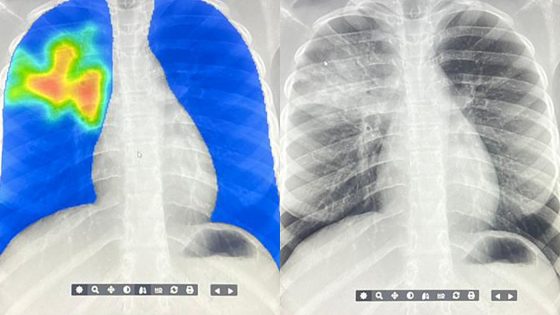

AI steps in to detect the world's deadliest infectious disease

There’s a global shortage of radiologists. Now artificial intelligence is helping speed up the diagnosis of tuberculosis in hard-to-reach communities.